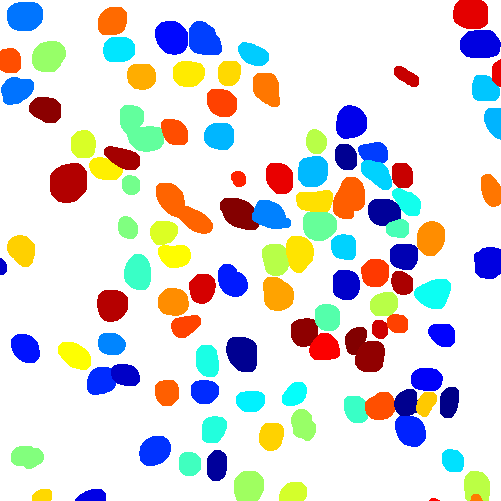

Figure 6 shows how our method segments the nuclei step by step. The color variety is well controlled by the color normalization procedure. The prediction result shows clear nuclear areas and nucleus boundaries. In the final segmentation result and ground truth image, each nucleus is represented by a different color.